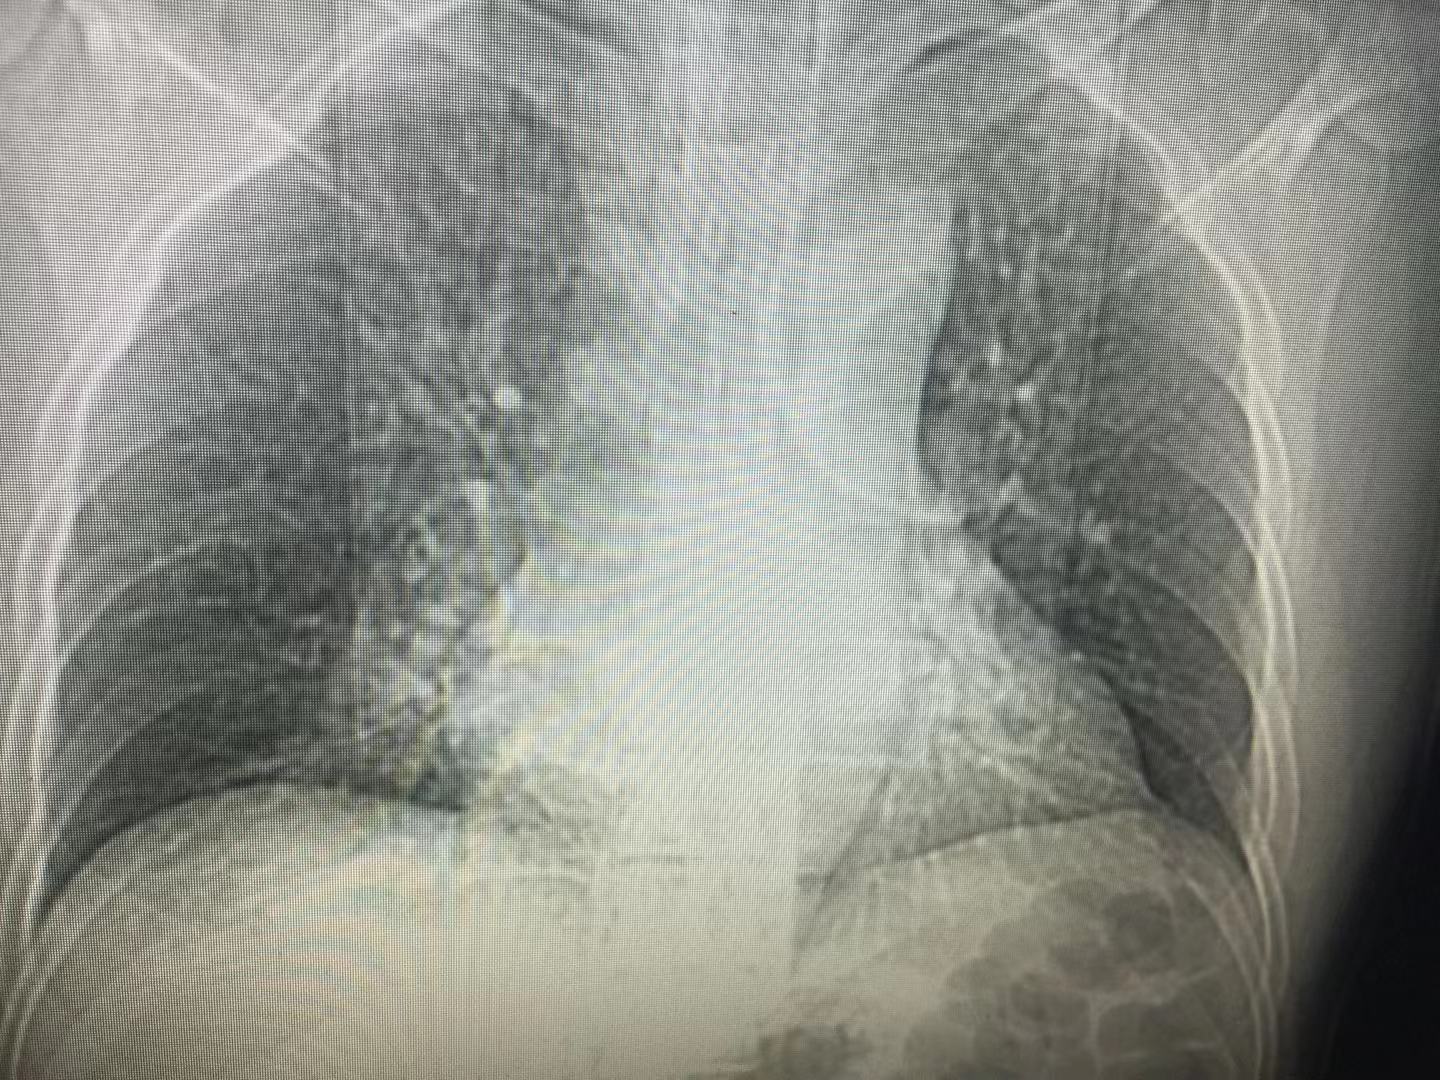

X光片

X光胸片是通过X线照射成像,直接透过整个胸腔或相应器官。其简单易行、辐射小、价格较低,可直观的看到心肺大小变化、肺部是否有阴影及边界模糊、气管位置改变及是否有液气胸、骨折损伤、异物等。对于普通肺炎,体检,疾病的初步排查都是首选。但它的缺点在于精密度不高,对于较小的病变、肿瘤灵敏度不够,且由于器官重叠会有一定的遮挡,这时就需要进行更精密的检测。